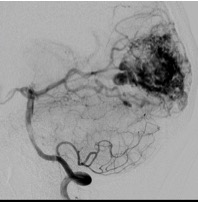

Brain arteriovenous malformation (AVM) is an abnormal tangle of poorly formed arteries and veins in the brain. These are risks for causing bleeding in the brain, in the form of subarachnoid hemorrhage and/or intracerebral hemorrhage.